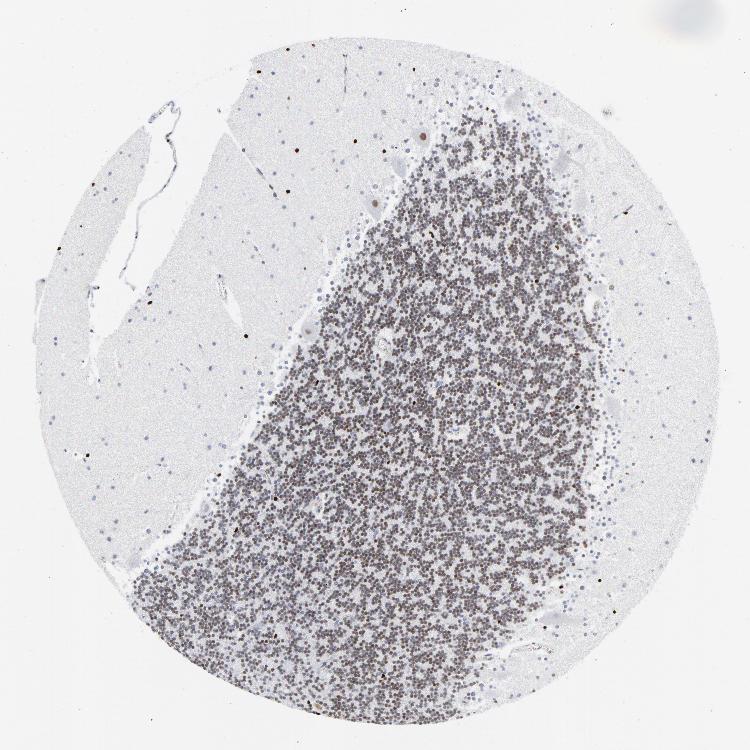

CEREBELLUM - Antibody stainingi

Antibody staining in the annotated cell types in the current human tissue is reported as not detected, low, medium, or high, based on conventional immunohistochemistry profiling in selected tissues. This score is based on the combination of the staining intensity and fraction of stained cells.

Each image is clickable and will lead to virtual microscopy that enables deeper exploration of all samples and also displays staining intensity scores, fraction scores and subcellular localization as well as patient and tissue information for each sample.

Antibody HPA021213Antibody CAB004321

Purkinje cells HighMedium

Cells in granular layer HighLow

Cells in molecular layer HighMedium